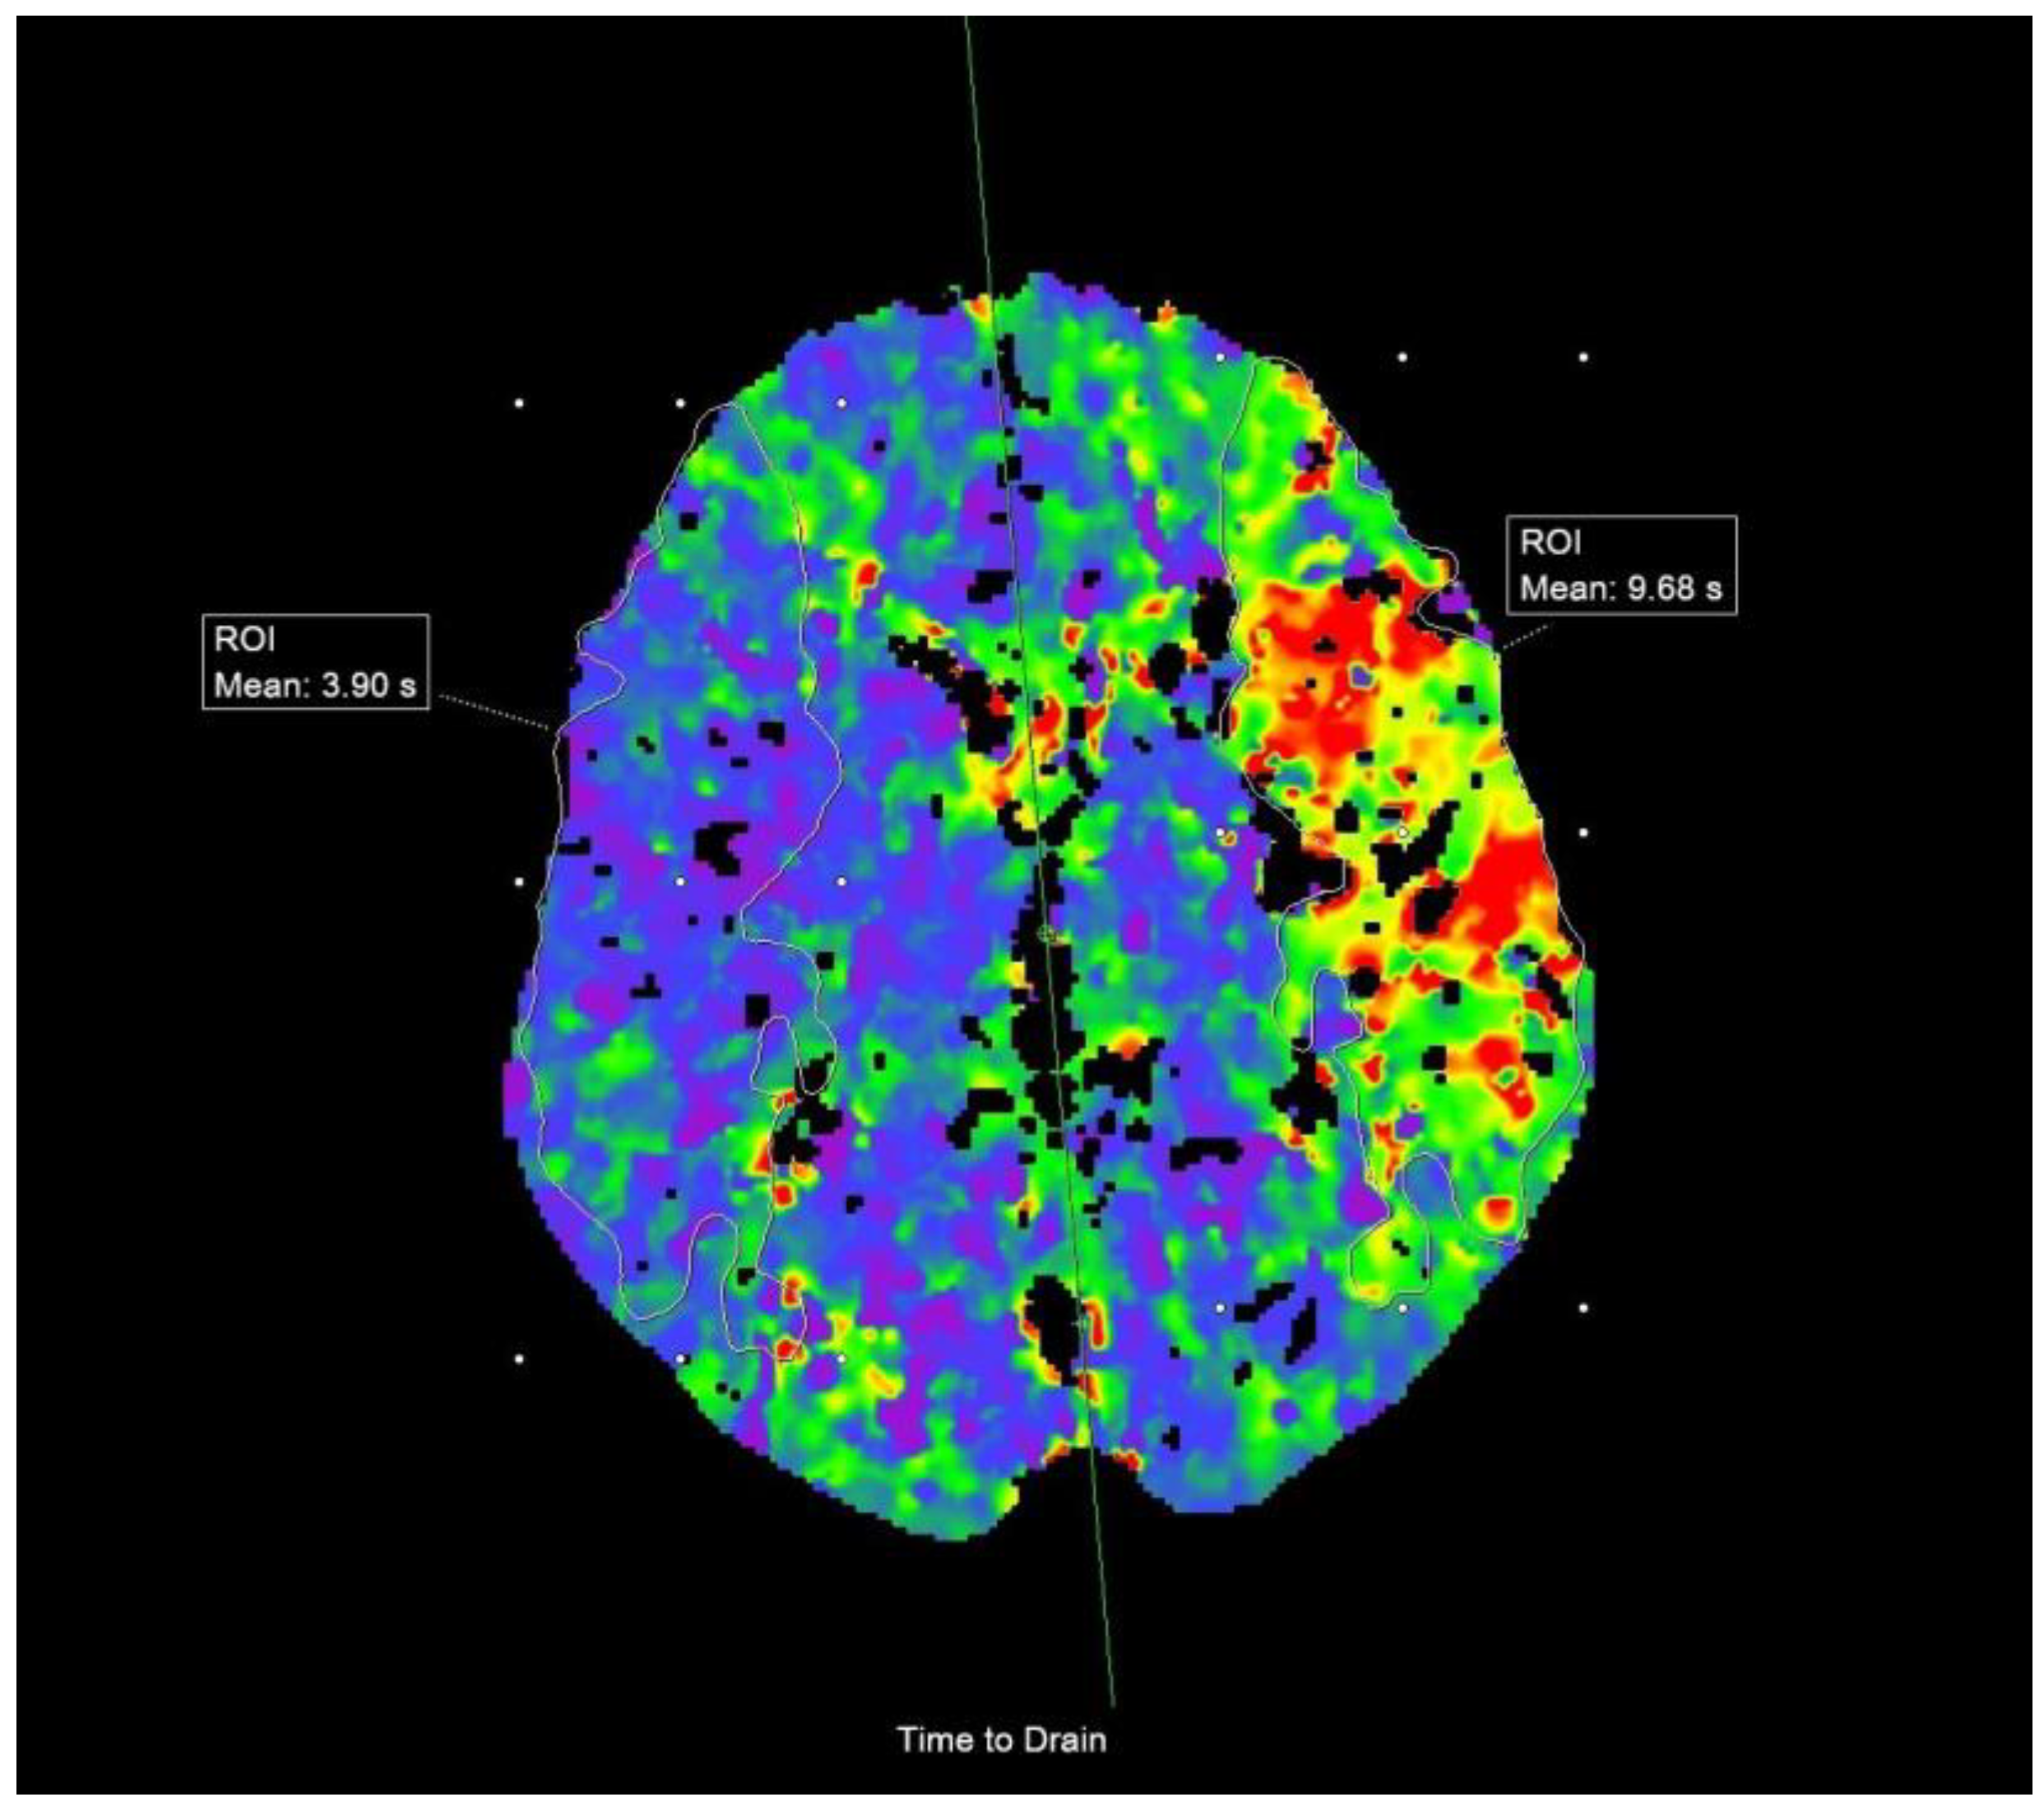

2.3. Imaging Data and Analysis